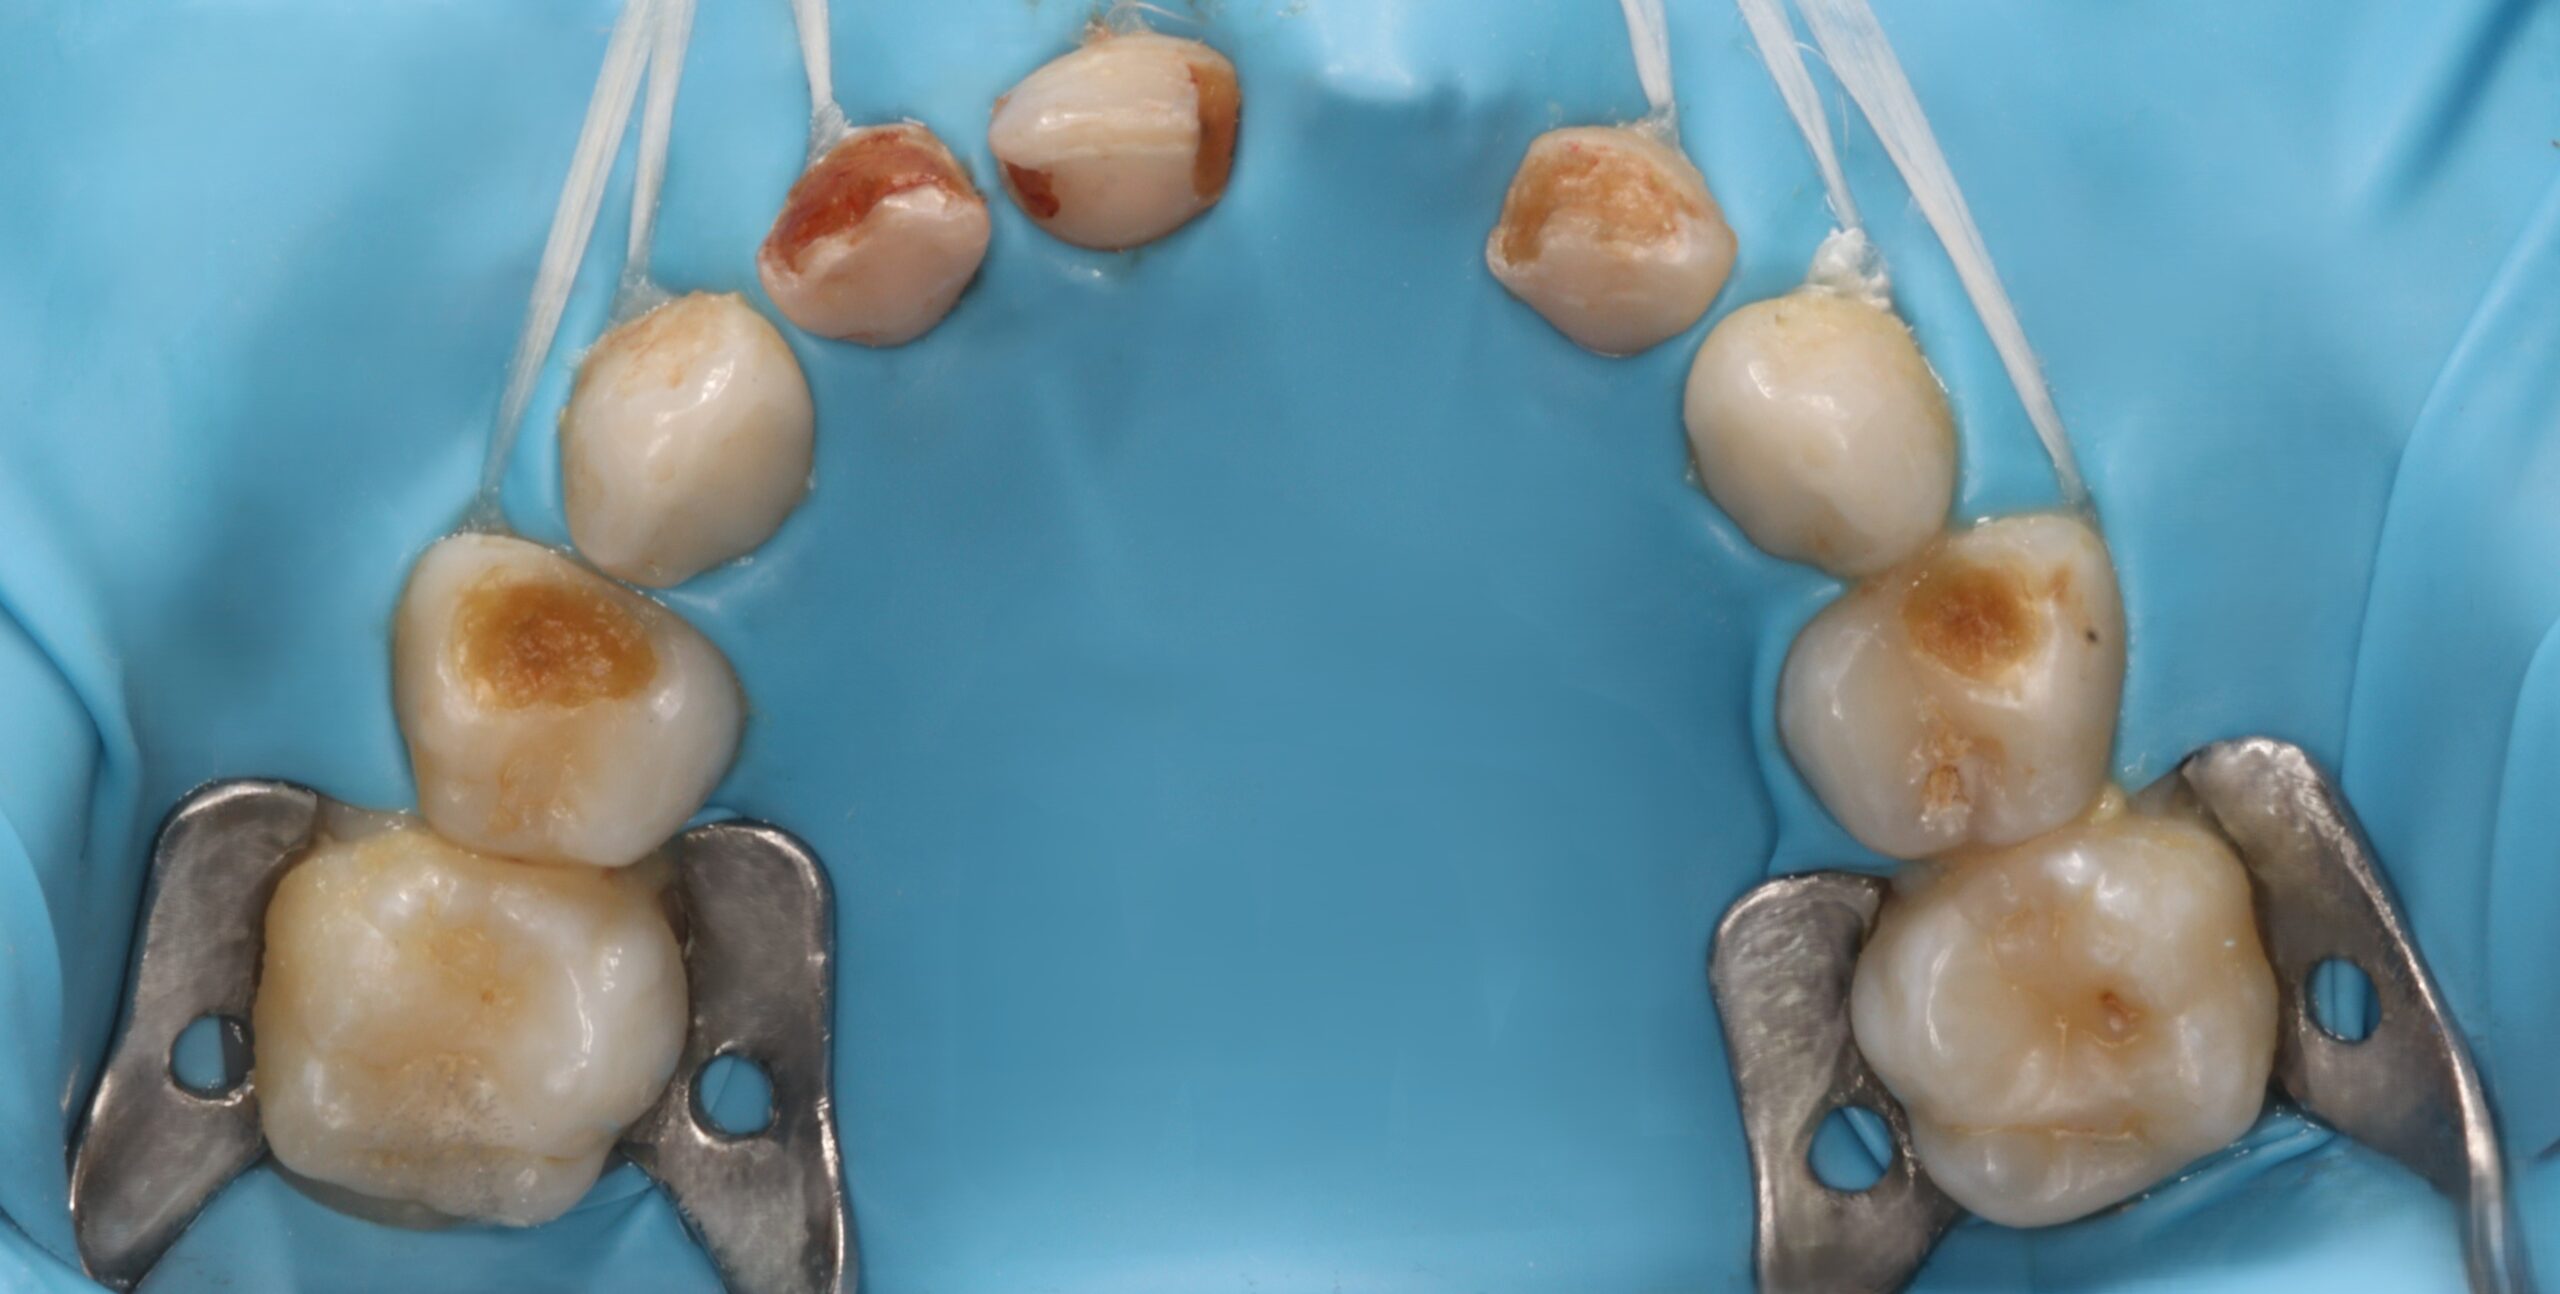

Быстрое и качественное лечение под наркозом и в закиси азота – её особенность.

- Специализируется на лечении кариеса постоянных зубов